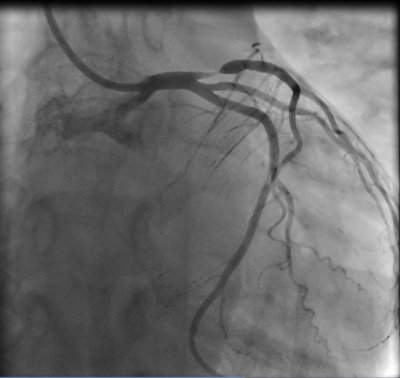

Mužská erekce je barometrem zdraví, porucha erekce je často prvním projevem závažného onemocnění, nejčastěji srdečně-cévního. Porucha mužské erekce může být důsledkem srdečně-cévního onemocnění a může až o 3 – 5 let předcházet srdeční infarkt či mozkovou mrtvici. Mladší muži od 35 do 50 let, kteří trpí středně těžkou nebo těžkou poruchou erekce, by z tohoto důvodu měli být vždy vyšetření s cílem vyloučit závažné onemocnění srdce a cév, zejména ischemickou chorobu srdeční.

Ve srovnání se zeměmi severní, západní a jižní Evropy máme vysoký počet nemocných s vysokým krevním tlakem, zvýšenou hladinou cholesterolu, v populaci narůstá počet obézních a jedinců trpících cukrovkou. Tyto rizikové faktory včetně kouření, fyzické inaktivity a sedavého způsobu života představují riziko pro rozvoj aterosklerózy, která je společným jmenovatelem ischemické choroby srdeční i poruchy erekce, erektilní dysfunkce.

V rámci detekce kardiovaskulárních onemocnění jsme vyšetřili 150 mužů přicházejících pro potíže s erekcí v průměrném věku 54 let (26-84 let). Šest z 10 nemocných trpělo hypertenzí, každý pátý byl diabetik, 63% mělo zvýšenou hladinu cholesterolu, 35% bylo obézních, každý čtvrtý byl kuřák.Vysoké riziko (> 5 %) možné fatální srdečně-cévní či mozkové příhody v následujících 10 letech jsme nalezli u 41 % mužů souboru. Významným vedlejším nálezem byla velmi nízká trénovanost a tolerance tělesné zátěže u českých mužů, kterou jsme zjistili při bicyklové ergometrii.